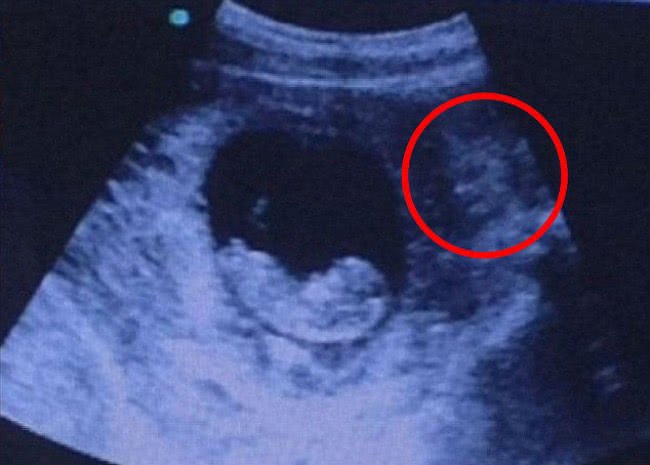

Een ‘griezelige’ echo - waarbij het lijkt of er een demon ‘waakt’ over een foetus in de baarmoeder - gaat momenteel viraal op het internet. De echo die werd geplaatst door een anonieme Imgur-gebruiker is inmiddels een miljoen keer bekeken in twee dagen.

De mensen die de echo gezien hebben, hebben zo allemaal hun eigen interpretatie van wat er nu daadwerkelijk te zien is op de foto. De echo laat een foetus zien van rond de acht tot tien weken oud, met naast de baarmoeder iets wat lijkt op een figuurtje met een dreigend gezicht en een naakt lichaam.

De Imgur-gebruiker schreef erbij: ‘Echo van een vriend. Als je het ziet…’ Gebruiker JosePhINCH was één van de eersten die het griezelige gezicht spotte: 'Er zit een demon rechts', terwijl Manshottothemoon zei: ‘Ziet niemand anders die demon rechts?’. Echter, andere gebruikers interpreteerden het figuurtje anders. Ene Jackbos schreef: 'Hindoeïstische godin aan de rechterkant van het beeld.' Subtlemrs zei: 'Ik zie een vriendelijke zeemeermin. Iedereen ziet een demon. We zijn allemaal raar. '

Toen honderden mensen naar de site gingen om meer informatie krijgen, moest de degene die de foto gepost had wel even een update geven. Luigivampa-over9000 verklaarde: 'Alles is prima nu. De baby was twee maanden te vroeg geboren. Ze vroegen degenen die de echo maakten wat dat nu was, maar men had niet echt een antwoord behalve dat ze zoiets nog nooit eerder gezien hadden. Best een interessant verhaal met een passende foto...’